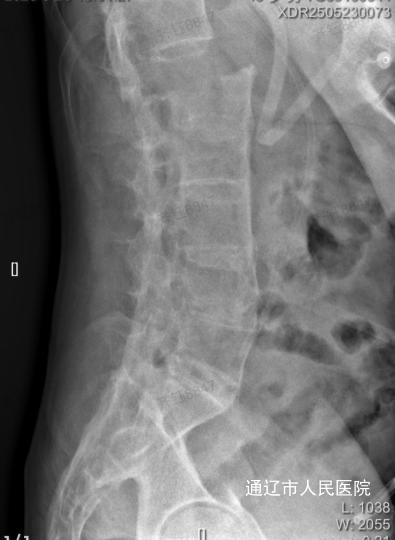

5月11日,43岁的患者包某某因强直性脊柱炎病史6年,身体状况不佳,又意外遭遇草料搅拌机绞伤胸腹部。伤后,患者随即出现腹痛、腰痛、呼吸困难等多种症状。紧急送医后,经检查确诊为左侧大量胸腔积液、少量腹腔积液、第1腰椎骨折伴滑脱,同时血压、血氧持续下降,病情极其危重,迅速被收入我院西院区急诊重症医学科(ICU)。